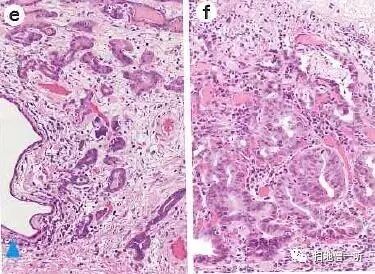

HE染色低倍镜观察可见病变区域以外的粘膜为胃体非萎缩粘膜,病变部(红色线部分)与周围粘膜不存在明显高度差。

HE染色中倍镜观察病变区域可见粘膜中层(腺颈部)腺窝上皮与胃底腺之间存在带状病变区域,淡嗜酸性胞浆的印戒细胞存在。

高倍镜观察腺颈部印戒细胞癌

最终病理诊断:

胃角大弯,O-IIb,10mm,sig,T1a (M),UL(-)